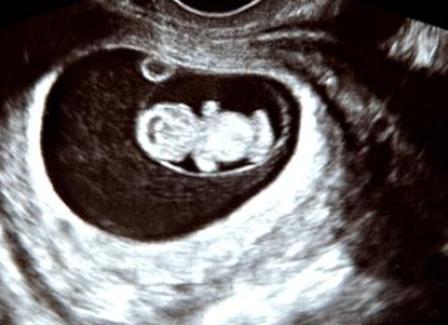

- Акушер использует УЗИ плода, чтобы проверить положение плаценты и ребенка.

Проведение амниоцентеза предлагается беременным женщинам, которых беспокоят возможные проблемы с развитием плода. Тест проводится между 15-й и 20-й неделями. Условия, при которых может потребоваться проведение теста, включают:

- Проблемы, обнаруженные на УЗИ плода